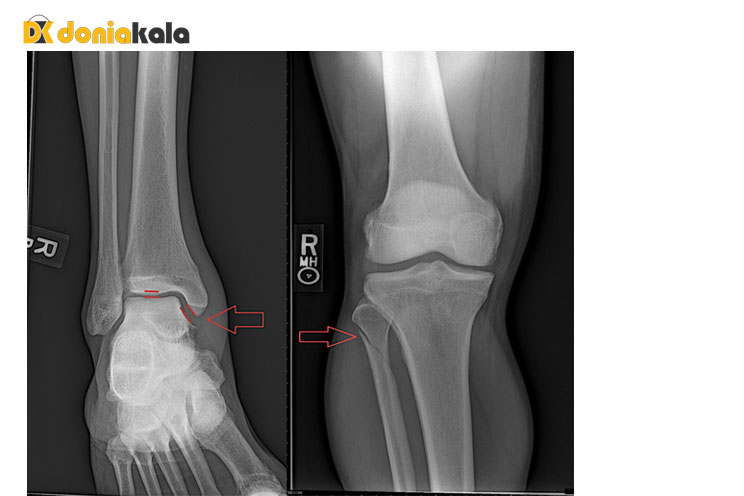

شکستگی مسیونونئو Maisonneuve: به عنوان مثال، شکستگی مسیونونئو Maisonneuve شامل از هم گسیختگی کامل رباط های اطراف مچ پا همراه با شکستگی فیبولا در سطح زانو است. برای این نوع آسیب، عکسبرداری با اشعه ایکس مچ پا ممکن است شکستگی را نشان ندهد یا بیثباتی مرتبط با این آسیب را نشان دهد، زیرا شکستگی استخوان واقعی به خوبی بالای مچ پا قرار دارد و آسیبهای رباط را فقط میتوان با سایر اشکال تصویربرداری مشاهده کرد. مانند ام آر آی